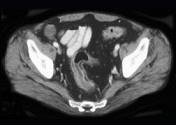

问题 男,35岁,腹痛、腹泻、腹胀、脓血便、里急后重,结合图像,选择最可能诊断 ( )

选项 A.溃疡性结肠炎 B.结肠克罗恩病 C.结肠结核 D.假膜性肠炎 E.结肠淋巴瘤

答案 A